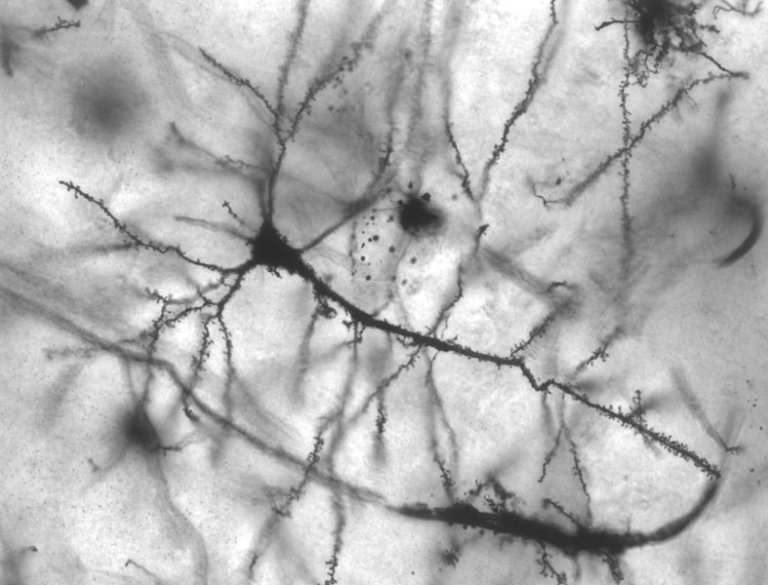

So what is actually going on in our brains when we mentally doze off? While neuroscientists haven’t fully pinned down all the mechanisms through which our brains work when we daydream, what we do know is that we likely form these alternate-reality thoughts with the assistance of a cluster of brain regions called the default mode network. Researchers have found that this network is most active when we aren’t focused on any concrete thing in the world around us.